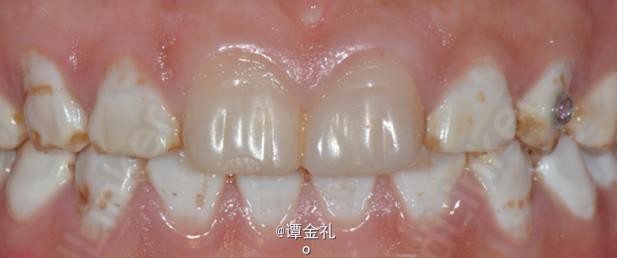

上 牙合 氟斑牙—美塑树脂贴面修复病例

患者,30岁,氟斑牙,上颌合平面右上倾斜。在他处已做两中切牙树脂贴面。平素体质好,无结核病、高血压、心脏病等病史。无药物、食物过敏。

计划:建议瓷贴面修复,由于种种原因未接受,要求树脂贴面修复